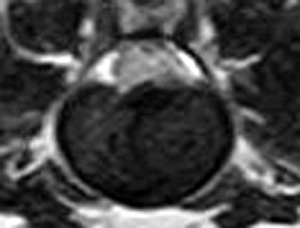

犬の多発性胸腰部椎間板ヘルニアのMRI検査

市外の先生からダックスちゃんの腰の痛みの精査依頼でMRI検査のご紹介がありました。検査結果から多発性胸腰部椎間板ヘルニアを認めました。その後かかりつけの先生のもとで内科治療となりました。